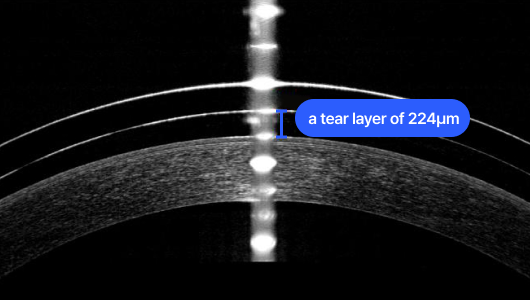

正確な診断のための最先端の特殊装置

ソウル・釜山パルグンセサン眼科では、円錐角膜を正確に診断するために先端特殊装備を備えて精密検査を施行しており、

前方と後方、角膜湾曲率、前方深さ、角膜直径など前眼部の全ての情報を把握しながら角膜後面まで精密分析を行い、

初期円錐角膜診断及び視力矯正術の安全性について正確に分析しています。